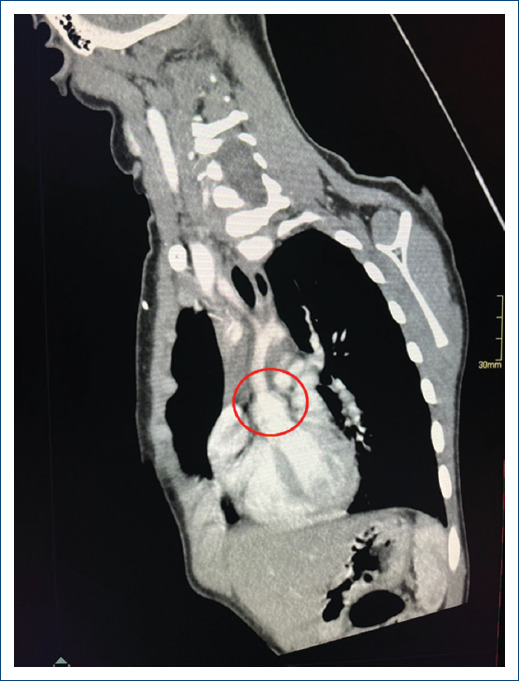

主动脉瓣上狭窄(SVAS)是一种与威廉姆斯-伯伦综合征有关的先天性畸形。其特点是窦管交界处严重狭窄。由于弹性蛋白基因的改变,平滑肌层增厚。治疗方法是外科手术,有几种缓解阻塞的技术,从单补片技术到用三个补片置换全部三个主动脉窦。然而,最佳技术仍不明确。本文旨在对 SVAS 的手术技术进行文献综述,并介绍罗伯托-吉尔伯特-埃利萨尔德医院对一名 4 岁婴儿应用 Doty 技术的情况。

Supravalvular aortic stenosis (SVAS) is a congenital malformation associated with Williams-Beuren syndrome. It is characterized by severe stenosis of the sinotubular junction. The smooth muscle layer is thickened due to an alteration of the Elastin gene. The treatment is surgical and there are several techniques to relieve obstruction which range from the single-patch technique to the replacement of all three aortic sinuses with three patches. However, the optimal technique is still unclear. The objective of this article is to carry out a bibliographic review of surgical techniques for SVAS and the description of the application of the Doty technique for a 4-year-old infant at the Roberto Gilbert Elizalde Hospital.